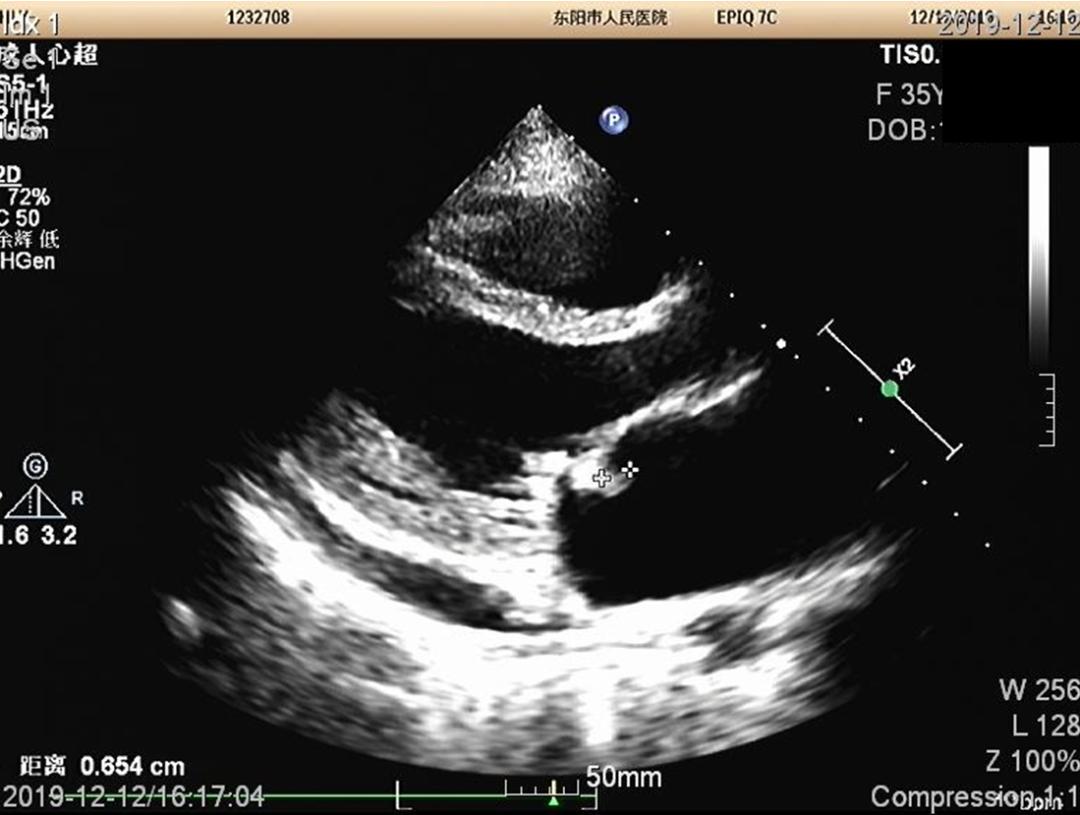

心超心尖四腔心切面,多普勒超声可见二尖瓣返流、返流束较窄。 二尖瓣存在前叶A2、A3区脱垂。

胸骨旁左室长轴切面,显示二尖瓣上有赘生物,这赘生物其他多个切面也可以观察到。

另结合患者血培养阳性,为草绿色链球菌,故诊断明确,为亚急性感染性心内膜炎。

这脾肾肠多脏器加上右髂总动脉,都为心源性栓塞,栓子为二尖瓣赘生物脱落的菌栓。